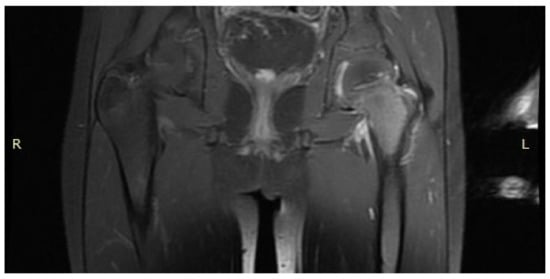

3.4. Case 4: OO Masking as a Fatigue Fracture